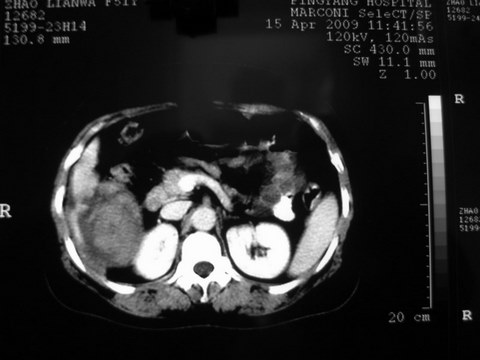

患者 女 51岁 两天前感觉上腹疼,无明显诱因,b超示肝右叶囊实性占位,边缘清楚,其内回声不均匀,ct增强如图,大家看看是什么 ,病人一年前及两月前b超检查只是提示胆囊炎

外院术后,证实肝癌合并出血

特点:1,病灶发展迅速,(2月前正常)[br] 2,囊实性,且并边界清晰光滑,呈右后叶赘生性。囊性区无强化,实性部分较多轻度强化,边界欠清。考虑囊腺癌或囊腺瘤。

出病理 中分化肝细胞癌合并出血